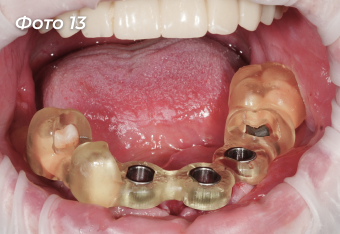

Через 4 месяца после первой операции было проведено оперативное вмешательство на нижней челюсти. Была выбрана другая тактика, были удалены сразу все зубы (Фото 11).  Установлено 6 имплантов  (Фото 12) по хирургическому шаблону  (Фото 13).